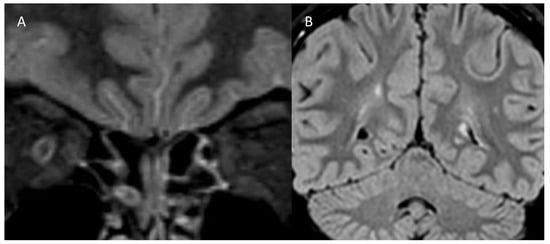

| MRI | Left optic nerve: hyperintensity (T2) Two millimetric T2 hyperintense cerebellar foci | Right optic nerve: hyperintensity (STIR), contrast enhancement ADEM outcomes | Right optic nerve: small hyperintensity (T2) Multiple juxtacortical, infratentorial, and periventricular demyelinating lesions; four lesions with contrast enhancement | Right and left optic nerves: retrobulbar bilateral swelling, contrast enhancement |